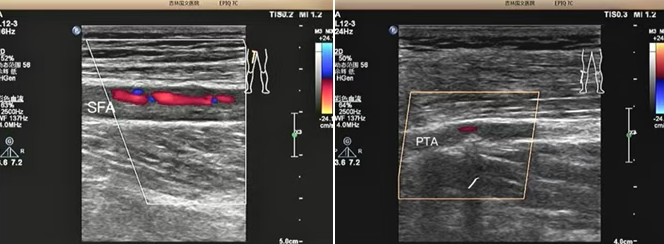

該患者是一位老年男性,因 “雙小腿麻木、發(fā)涼 2 個(gè)月” 前來(lái)我院就診。超聲科為其進(jìn)行下肢動(dòng)靜脈彩超檢查時(shí),精準(zhǔn)發(fā)現(xiàn)其股淺動(dòng)脈及脛后動(dòng)脈存在重度狹窄至閉塞的情況。超聲檢查憑借其無(wú)創(chuàng)、便捷的獨(dú)特優(yōu)勢(shì),在第一時(shí)間就為臨床治療提供了準(zhǔn)確無(wú)誤的診斷依據(jù),為后續(xù)治療方案的制定奠定了堅(jiān)實(shí)基礎(chǔ)。

超聲檢查以其無(wú)創(chuàng)、便捷、可重復(fù)的顯著優(yōu)勢(shì),在此次診療過(guò)程中發(fā)揮了重要作用,清晰地顯示了患者下肢動(dòng)脈的病變情況:1、準(zhǔn)確判斷病變部位:精準(zhǔn)定位到股淺動(dòng)脈及脛后動(dòng)脈。2、明確病變程度:確定為重度狹窄至閉塞。3、評(píng)估側(cè)支循環(huán)建立情況:為治療方案的制定提供了關(guān)鍵參考。